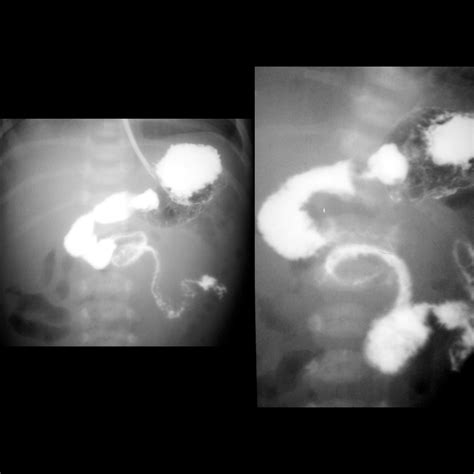

• Barium Enema: A test where a contrast dye is inserted into the rectum, and X-rays are taken to visualize the colon and rectum.